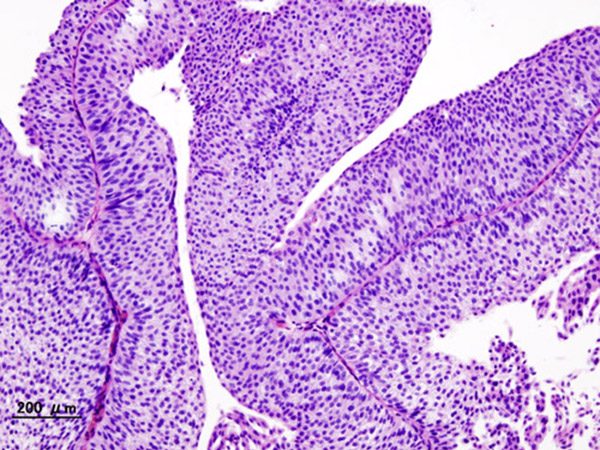

Cancer isn’t a single disease. The term cancer encompasses many diseases all characterized by the uncontrolled proliferation of cells. Ignoring the body’s signal to stop, malignant cells multiply to form tumors in organs and tissues or, in the case of blood cancers, crowd out normal cells in the bloodstream and bone marrow.